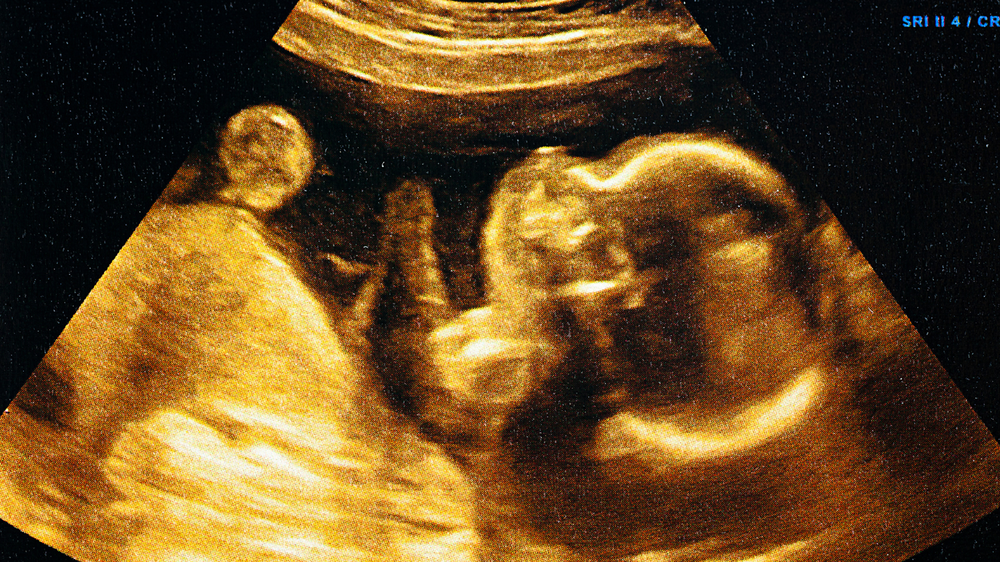

Foetal breathing movements in the third trimester show that a baby is growing well. While the baby does not yet breathe air, these gentle, regular motions indicate that the lungs and nervous system are developing as they should. Watching for these movements helps parents and doctors monitor the baby's health.

By the third trimester, pregnancy enters its most crucial phase. Each movement in the womb—a kick, twist, or rhythmic flutter—reflects development. Among these, foetal breathing movements (FBMs) are especially significant.

FBMs are not true breaths, as the baby is surrounded by amniotic fluid. Instead, FBMs are gentle rhythmic contractions of the diaphragm and chest muscles that prepare the lungs for life outside. Observing these movements offers profound insight into a baby’s growth and health, particularly in the Indian context, where prenatal monitoring is increasingly accessible.

Foetal breathing movements arepractice motions. Instead of inhaling air, the baby moves amniotic fluid in and out of the lungs. This strengthens and matures the respiratory system before birth.

• They are often observed through ultrasound scans.